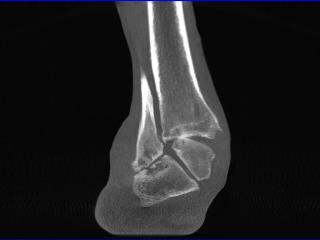

Das pedCAT ist die erste Praxislösung eines digitalen Volumentomografen ( englisch: Conebeam) für den Fuss- und Sprunggelenk Chirurgen. Das Gerät ermöglicht die Diagnostik mit Hilfe eines pyramidenförmigen Röhrenstrahles und eines Flachbilddetektors, die sich 360° um den Patienten drehen und sowohl belastete als auch teilbelastete Untersuchungen von Fuss- und Sprunggelenken zulassen. Innerhalb von 68 Sek. ist die Untersuchung von beiden Füssen abgeschlossen, die Bildrekonstruktion erfolgt in 3,5 Minuten.

• 2D- und 3D-Bildakqusition und Darstellung beider Füsse und Sprunggelenke mit oder ohne Belastung

• Darstellung dreidimensionaler Details, die mit konventionellen Röntgenbildern nicht darstellbar sind

• 3D-Darstellung unter Belastung, was mit konventioneller Computertomographie nicht möglich ist